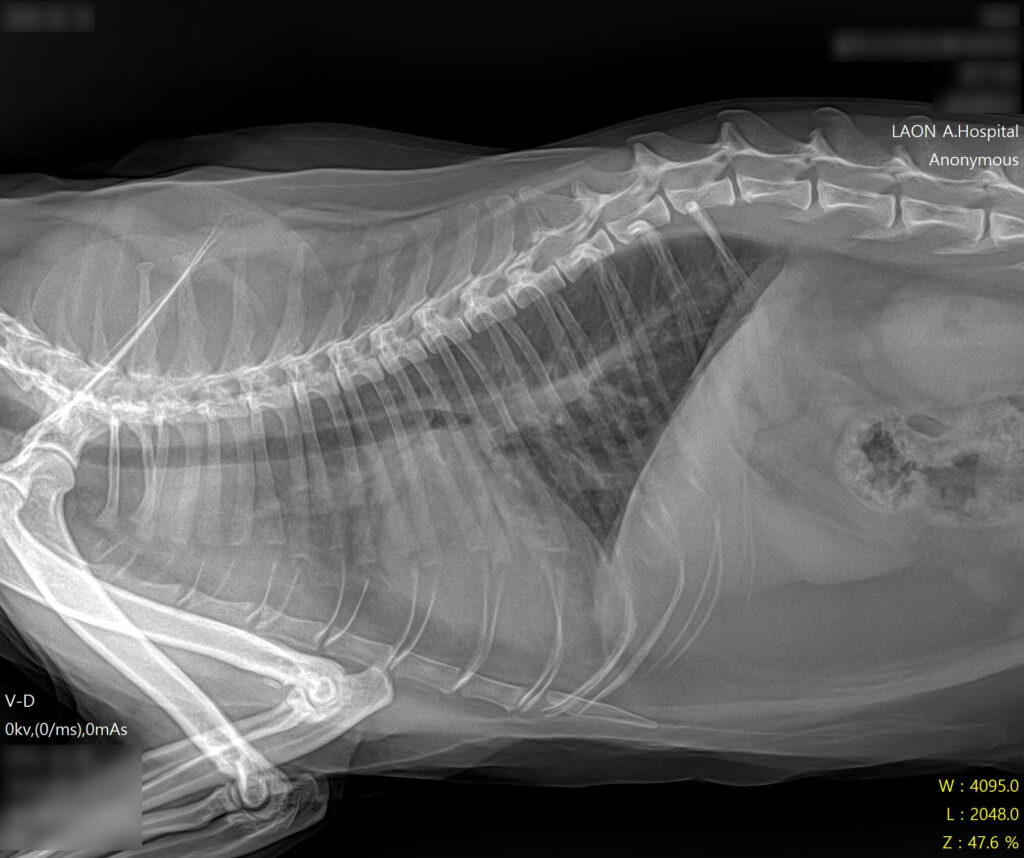

* 폐야가 하얗게 변한 폐수종 소견과 비대해진 심장 확인

- 방사선 검사: 흉부 방사선 촬영 결과, 폐 전반에 걸친 폐부종(pulmonary edema) 소견이 확인되었습니다. 또한 심장의 실루엣이 전형적인 ‘Valentine Shape(발렌타인 하트 모양)’으로 관찰되었는데, 이는 HCM(비대성 심근병증)에서 나타나는 특징적인 방사선 소견입니다.

* 폐수종 개선 및 깨끗해진 폐야 확인